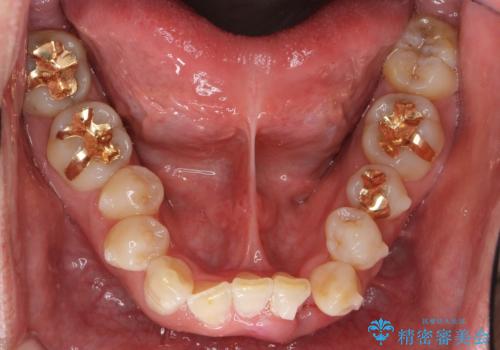

仕上がりに限界はありましたが、比較的短期間で歯並びが整いセラミック治療を行うことができ、患者様に「治療して良かった」とご満足頂けました。

犬歯は歯根が長く寿命も長い歯で、咀嚼機能時も重要な役目を果たすため、基本的に矯正の便宜抜歯に選択する歯ではありません。(一般的には第一小臼歯もしくは第二小臼歯が選択されることが多いです)

本症例では、様々な抜歯パターンの3Dシミュレーションを行い患者様と相談を重ねリスクをご理解頂いた上で、患者様のご希望により例外的に犬歯の抜歯を行いました。

小臼歯の歯根長が長いことを治療前にレントゲンで確認し抜歯部位を決定しました。

側方運動時に大きな役割をもつ犬歯がないため、今後の定期健診で歯の状態を注意深く観察していく必要があります。